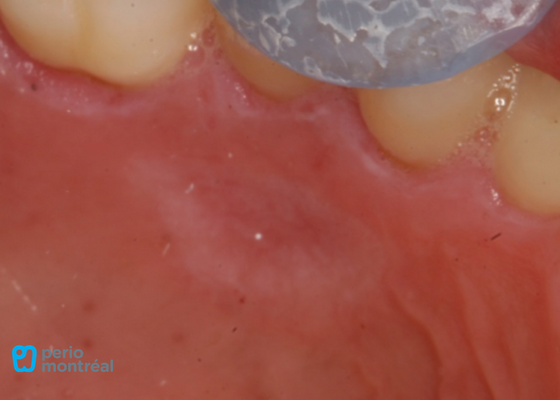

Final result

Our primary goal of increasing the width of keratinized tissue is achieved, and we are able to get almost 100% root coverage as well in one surgical procedure. Both the patient and surgeon were very happy with the result!